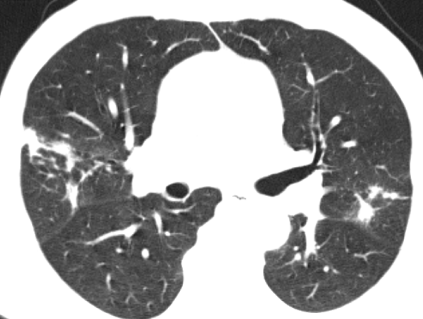

入住肺病科(呼吸内科)后,医生为患者完善了胸部CT及相关检查。影像结果显示:“双肺见片状密度增高影及实变影,边界模糊,提示双肺感染。”针对患者病情,科室立即组织了病例讨论。专家们凭借着深厚的医学知识和丰富的临床经验,深入分析病情,制定出了科学合理的诊疗方案,一天内完成了相关检查。

治疗前CT影像▲